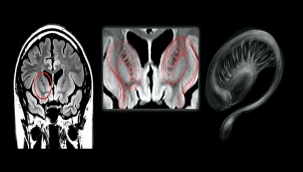

UFO ile karşılaşan pilotların beyinleri incelendi -